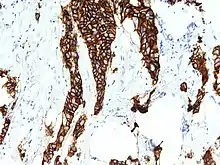

Her 2 staining on patient breast cancer tissue identified as stage 3

The staining is seen as a cell membrane with continuous brown color.

Tests are usually performed on breast biopsy samples obtained by either fine-needle aspiration, core needle biopsy, vacuum-assisted breast biopsy, or surgical excision. Immunohistochemistry is used to measure the amount of HER2 protein present in the sample. Examples of this assay include HercepTest, Dako, Glostrup, and Denmark. The sample is given a score based on the cell membrane staining pattern.

Immunohistochemistry

Score[36][37]Status[36][37]Pattern

0HER2 negative

(not present)

Negative for HER2 protein expression.[38]

1+Weak or incomplete membrane staining in any tumor cells.[38]

2+Borderline/Equivocal

• Complete membrane staining that is either nonuniform or weak in intensity, but has circumferential distribution in at least 10% of cells.[37][38]

or

• Uniform intense membrane staining in 30% or less of tumor cells.[38]

3+HER2 positiveUniform intense membrane staining of more than 30% of invasive tumor cells.[37][38]